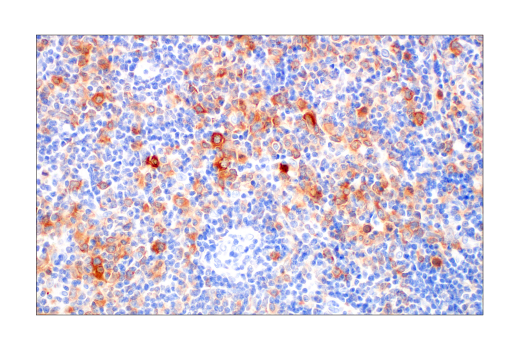

W, IHC-Bond, IHC-P, FC-FP

W: Western Blotting IHC-Bond: IHC Leica Bond IHC-P: Immunohistochemistry (Paraffin) FC-FP: Flow Cytometry (Fixed/Permeabilized)